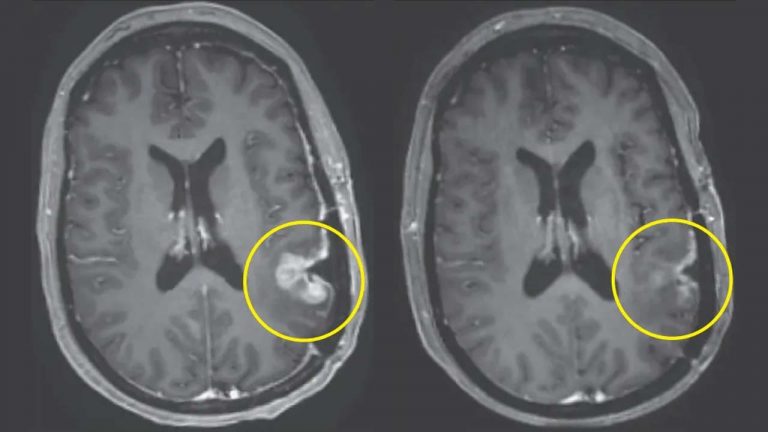

Brain Cancer: బ్రెయిన్ క్యాన్సర్ కు కొత్త చికిత్స.. ఒకే డోసుతో రోజుల్లోనే ట్యూమర్లు మాయం

శరీరంలోని కణాల అసాధారణ పెరుగుదల పలు రకాల క్యాన్సర్లకు దారితీస్తుంది. వాటిల్లో ఒకటి బ్రెయిన్ క్యాన్సర్. మెదడులోని కణాల అసాధారణ పెరుగుదల దీనికి కారణం అవుతుంది. ఇది మెదడులో కణితుల పెరుగుదలకు దారితీస్తుంది. ప్రాధమిక మెదడు కణితులు బ్రెయిన్ లోనే పుట్టుకొస్తాయి. ద్వితీయ కణితులు శరీరంలోని ఇతర భాగాల నుంచి మెదడుకు వ్యాపిస్తాయి. బ్రెయిన్ క్యాన్సర్ కు గురైన వ్యక్తుల్లో తలనొప్పి, మూర్ఛలు, దృష్టి సమస్యలు, జ్ఞాపకశక్తి కోల్పోవడం, గందరగోళం, వికారం, వాంతులు వంటివి సాధారణ లక్షణాలు…